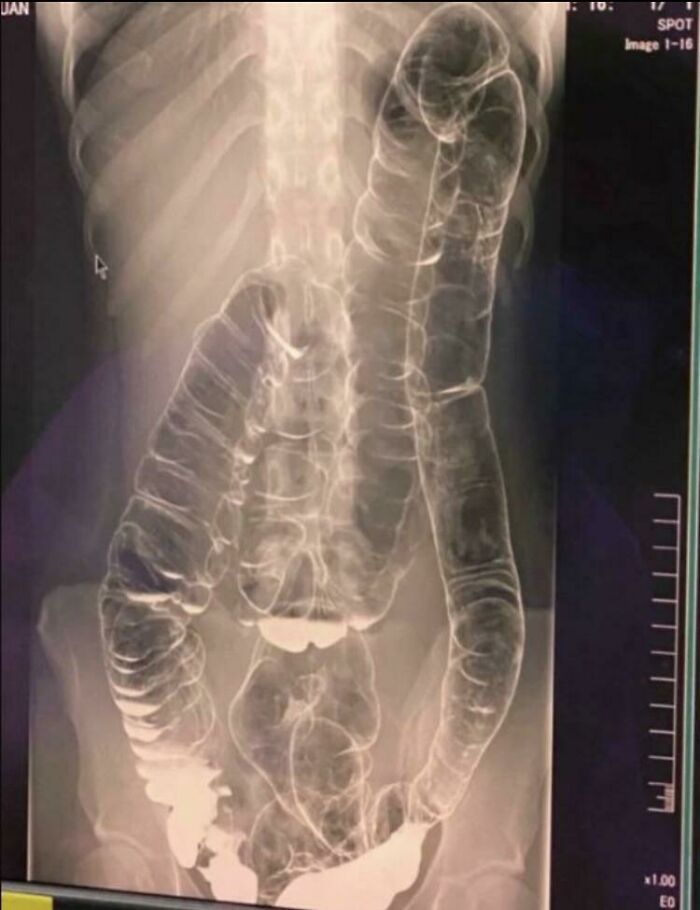

Reconstrucción de paladar y labio leporino doble